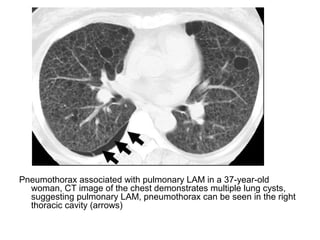

Pneumothorax associated with pulmonary LAM in a 37-year-old

woman, CT image of the chest demonstrates multiple lung cysts,

suggesting pulmonary LAM, pneumothorax can be seen in the right

thoracic cavity (arrows)